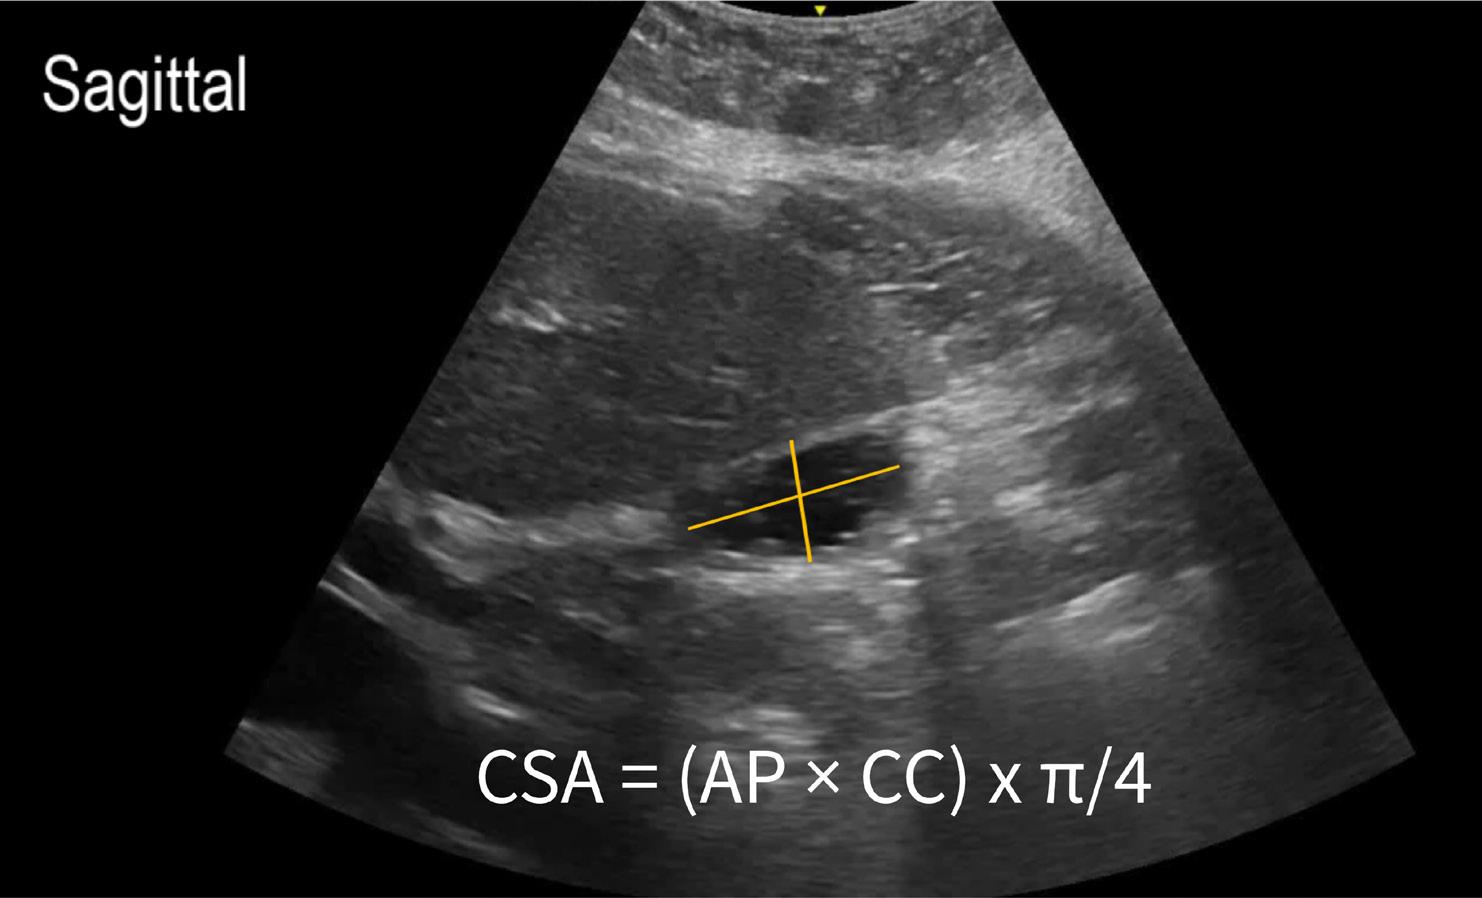

Patient’s Clinical Status

Clinical status ultimately guides therapy decisions regardless of the ingested agent (beta blocker, DHP calcium channel blocker or non-DHP calcium channel blocker), and HIET is likely appropriate for initiation when there is evidence of reduced cardiac contractility. If a bedside echocardiogram or ultrasound reveals a reduced ejection fraction, initiating HIET for inotropic support may be beneficial, even with DHP calcium channel blocker toxicity, to improve contractility and perfusion. Other therapies that have been tried in cases of refractory vasoplegia include nitric oxide scavengers such as methylene blue and hydroxocobalamin.

HIET should be titrated every 15 to 30 minutes as needed, based on cardiac output parameters (contractility and perfusion) and blood pressure:

• Contractility: Assess by bedside ultrasound in the emergency department. Increase HIET rate if ejection fraction is less than 50 percent.